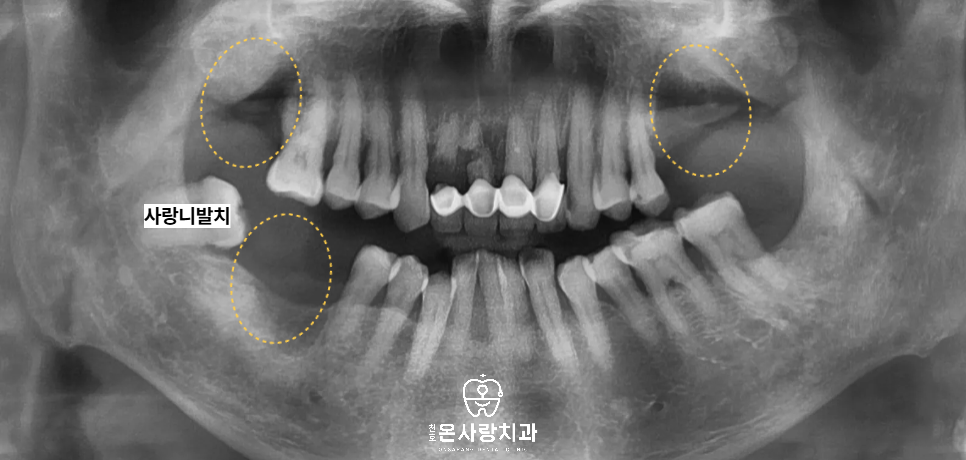

천호동치과에 처음 내원하셨을 때

왼쪽 위와 오른쪽 위아래의 어금니는

이미 상실되어 치아가 없는 상태였습니다.

그 중 오른쪽 위의 큰어금니는

정밀 검사 결과 뿌리와

주변 치조골 상태가 비교적 양호하여,

신경치료 후 엔도 및 크라운을 통해

치아를 살리는 방향으로 계획하였습니다.

기능과 수명을 모두 고려했을 때

자연치아를 유지하는 것이

환자분께 가장 유리하다고

판단했기 때문입니다.